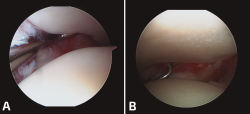

En las lesiones agudas de la sindesmosis sin fractura, lo que hallamos más frecuentemente es la interposición de partes blandas en el receso medial, que corresponde a la rotura o restos fibróticos de las estructuras ligamentosas del complejo medial. Es fundamental su desbridamiento para confirmar la reducción (Figura 3).

Figura 3. A: reducción correcta del peroné en su fosita tibial; B: palpamos la inestabilidad.